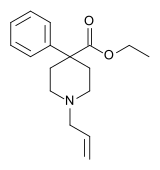

There are a number of broad classes of opioids:[260]

Phenylpiperidines

- Pethidine (meperidine)

- Ketobemidone

- MPPP

- Allylprodine

- Prodine

- PEPAP

- Promedol